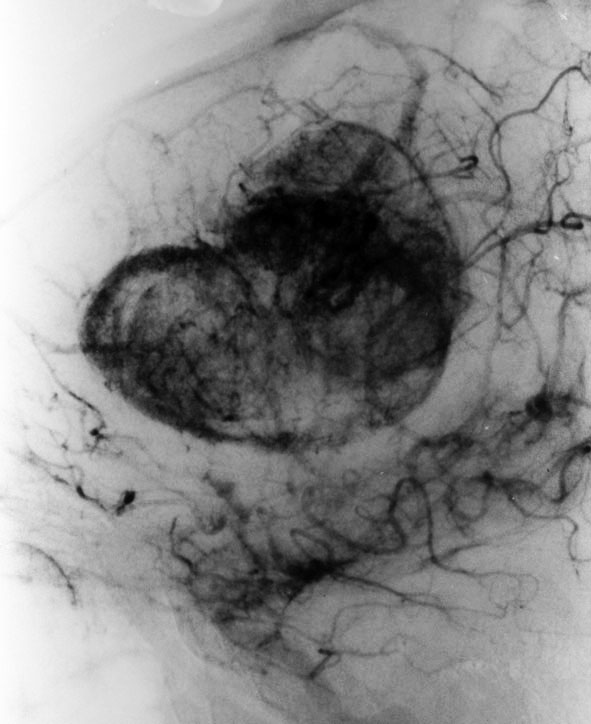

前頭葉にできた悪性黒色腫 malignant melanomaの脳血管撮影像です。腫瘍は強く濃染して大きな導出静脈があります。開頭手術で腫瘍を摘出しようとするとものすごく出血しました。局所放射線治療やダカルバジンの化学療法を行ないましたが全く無効でした。